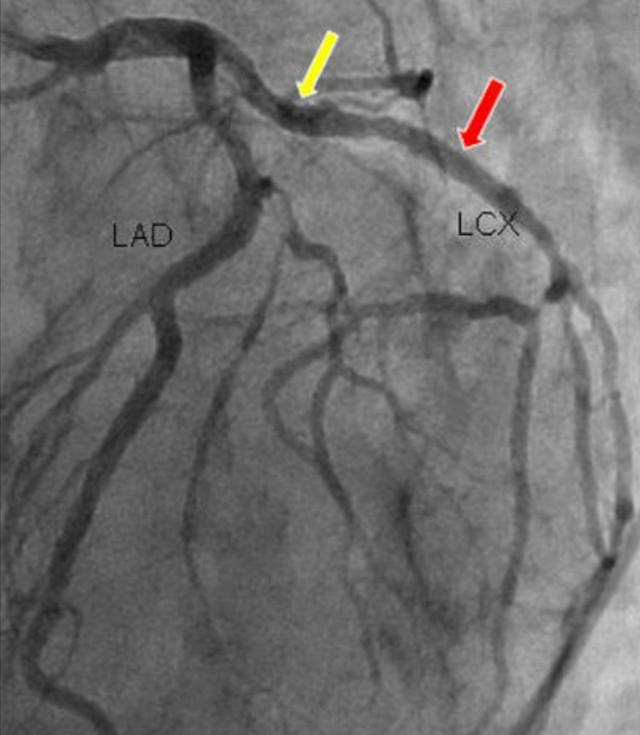

Mais ensuite.Depuis l'échographie, la tomodensitométrie coronaire et surtout la coronarographie, le diagnostic de la maladie coronarienne n'est plus un problème.Il s'agit notamment de pouvoir voir exactement quel vaisseau sanguin du cœur est bloqué et dans quelle mesure chez ce patient.

Il s'agit d'introduire un tube dans le cœur et d'effectuer une imagerie sélective qui permet de voir les vaisseaux sanguins à l'endroit voulu et de déterminer la quantité de vaisseaux sanguins obstrués.

Il est donc important de rappeler que la coronarographie est l'examen de référence pour le diagnostic de la maladie coronarienne, tandis que la tomodensitométrie coronarienne ne peut être qu'un test de dépistage.

En fait, ce n'est pas vrai. Rappelez-vous, les gens.La coronarographie implique l'insertion d'un tube dans le cœur, ce qui est un examen invasif et coûteux, et le patient doit souvent être admis à l'hôpital avant que l'examen puisse être effectué.Par conséquent, pour certains cas qui ne sont pas particulièrement typiques, nos médecins soupçonnent que la possibilité d'une maladie coronarienne n'est pas particulièrement élevée, ils laisseront tout de même le patient effectuer un scanner coronarien pour effectuer un premier dépistage, et s'ils ont un degré de suspicion élevé, ils continueront à choisir l'angiographie coronarienne !

En général, la maladie coronarienne est diagnostiquée lorsque la coronarographie montre une sténose coronarienne ≥50%, alors qu'une sténose coronarienne <50% ne peut être qualifiée que d'athérosclérose coronarienne.

6. angiographie coronaireLa coronarographie est un examen invasif qui reste l'"étalon-or" pour le diagnostic de la maladie coronarienne.. La localisation des lésions sténosées peut être identifiée et leur étendue estimée. Il est généralement admis qu'une réduction du diamètre de la lumière de 70 à 75 % ou plus affecte gravement l'apport sanguin.

2, CTA coronaire : il est considéré comme l'un des deux tests les plus importants pour les patients souffrant de maladie coronarienne, il permet de voir visuellement les vaisseaux sanguins avec ou sans blocage de sténose, mais comme il s'agit d'une image statique, il y a un certain degré de variabilité, et ne peut que déterminer la présence ou l'absence de blocage de sténose, pour fournir un support pour l'imagerie ultérieure ou non.

3. Coronarographie : si l'angiographie coronarienne est l'étalon argent pour le diagnostic de la maladie coronarienne, nous appelons la coronarographie l'étalon or, qui ne doit avoir l'opinion de personne, c'est le test le plus précis pour confirmer le diagnostic de la maladie coronarienne, il n'y a personne.

La tomodensitométrie coronaire est un test non invasif qui permet de détecter la présence et l'étendue d'une sténose de l'artère coronaire, tandis que l'angiographie coronaire est l'examen de référence pour le diagnostic de la maladie coronaire, qui permet de détecter l'emplacement et l'étendue de la sténose et de procéder à une intervention.